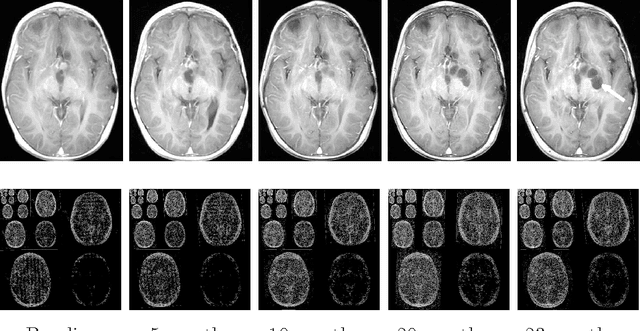

Abstract:Purpose: Repeated brain MRI scans are performed in many clinical scenarios, such as follow up of patients with tumors and therapy response assessment. In this paper, the authors show an approach to utilize former scans of the patient for the acceleration of repeated MRI scans. Methods: The proposed approach utilizes the possible similarity of the repeated scans in longitudinal MRI studies. Since similarity is not guaranteed, sampling and reconstruction are adjusted during acquisition to match the actual similarity between the scans. The baseline MR scan is utilized both in the sampling stage, via adaptive sampling, and in the reconstruction stage, with weighted reconstruction. In adaptive sampling, k-space sampling locations are optimized during acquisition. Weighted reconstruction uses the locations of the nonzero coefficients in the sparse domains as a prior in the recovery process. The approach was tested on 2D and 3D MRI scans of patients with brain tumors. Results: The longitudinal adaptive CS MRI (LACS-MRI) scheme provides reconstruction quality which outperforms other CS-based approaches for rapid MRI. Examples are shown on patients with brain tumors and demonstrate improved spatial resolution. Compared with data sampled at Nyquist rate, LACS-MRI exhibits Signal-to-Error Ratio (SER) of 24.8dB with undersampling factor of 16.6 in 3D MRI. Conclusions: The authors have presented a novel method for image reconstruction utilizing similarity of scans in longitudinal MRI studies, where possible. The proposed approach can play a major part and significantly reduce scanning time in many applications that consist of disease follow-up and monitoring of longitudinal changes in brain MRI.